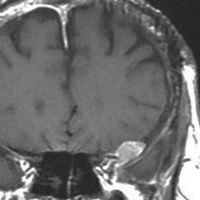

典型的な髄膜腫

この髄膜腫は中程度の大きさのものです。円蓋部髄膜種という最も多い最も手術の簡単なタイプです。麻痺や失語症やてんかんなどの症状はありません。とても美しくて若い女性の髄膜腫でしたが,子供に遺伝はしませんし,癌などと違ってタバコなどこれといった原因がなくて発生するものです。

MRIでの髄膜腫の見え方は撮影の仕方によっていろいろです。左からT1強調画像,T2強調画像,フレア画像といいます。腫瘍の横に小さく白い領域がありますが,これは脳の腫れた部分で脳浮腫といいます。髄膜腫があると周囲に脳浮腫が生じることがあります。

最も見やすいのが,ガドリニウム造影剤を注射して撮影するものです。一般的に髄膜腫は造影剤で白く映し出されます。この腫瘍は左脳側にあります。MRIの軸面という輪切りの写真では左右が逆になりますから注意してください。脳を下から見た図になっています。MRIはいろいろな方向から腫瘍を見ることができますが,右は冠状断という正面から見た図です。よく見ると腫瘍の上と下のはじっこに線状に糸を引いたように造影される部分があります。これをテールサイン(しっぽのサイン)といいます。腫瘍が硬膜に沿って延びている可能性があることを示しています。